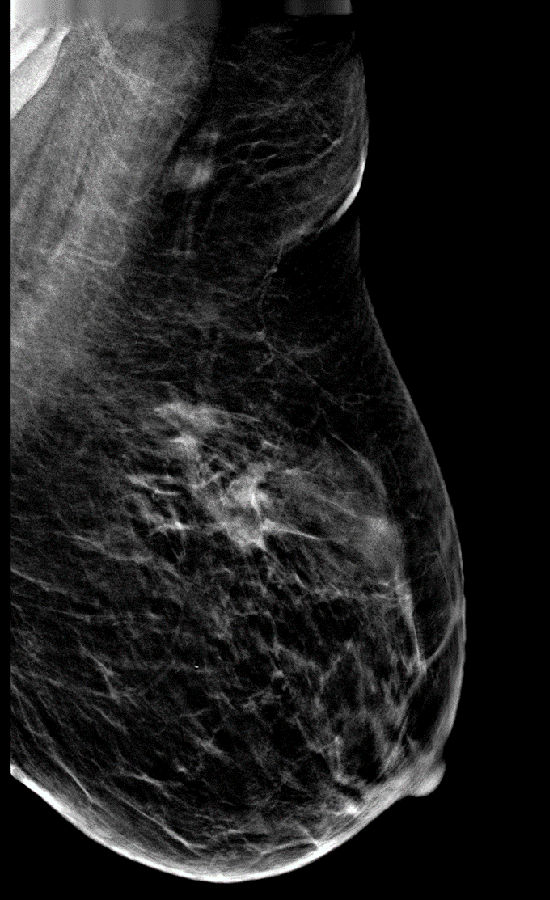

病史:患者,女,59岁,左乳肿块2月余。

DBT图像:

常规2D图像MLO位和CC位外上象限见局限密度增高影,其内似见钙化影,在DBT的薄层图像上观察病变范围比2D图像的范围要大些,病变周边见长短不一毛刺,其内见多个细点样钙化影。

左乳局限致密伴钙化,BI-RADS 4C 。

该病变结合DBT图像上的影像表现可以初步诊断左乳局限致密伴钙化为BI-RADS  4C 。